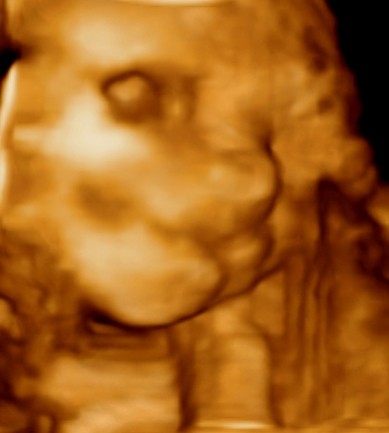

Melduje sie po usg!!! dzieciatko zdrowe:serce,mozg,nerki,watroba,zoladek ,rączki,nozki,pepowina,lozyzko -wszystko tak jak byc powinno!!

Troche to trwalo,bo ciezko bylo naklonic dzieciatko do wspolpracy

Waga 410g.Wiec inna waga niz na poranny usg ale to malutkie roznice.zupelnie bez znaczenia.

A to....Nasza córkA!!!!